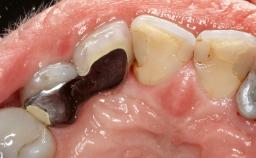

Peripheral Giant-cell Granuloma Associated with Peri-implant Tissues

Giant-cell granulomas (GCG) of the jaws are benign reactive lesions of unknown etiology, unrelated to giant-cell tumors (osteoclastomas), which are defined as benign but locally destructive and aggressive neoplasms (Jundt and coworkers 2005). Depending on their localization at the initial diagnosis, GCG are dived into central (CGCG) and peripheral (PGCG) types. CGCGs occur within the jawbones and appear as unilocular or multilocular radiolucent lesions. The incidence in the general population is very low. They are more commonly found in the mandible, mainly in children and young adults—patients are generally younger than 30 years—and have a greater incidence in females (Heithersay and coworkers 2002). The clinical behavior of CGCGs varies from slowly growing asymptomatic swellings to aggressive lesions that may result in pain, cortical perforation of the affected jaw site, and root resorption (de Lange and coworkers 2007).